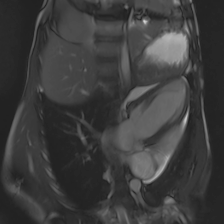

Accurate segmentation and motion estimation of myocardium have always been important in clinic field, which essentially contribute to the downstream diagnosis. However, existing methods cannot always guarantee the shape integrity for myocardium segmentation. In addition, motion estimation requires point correspondence on the myocardium region across different frames. In this paper, we propose a novel end-to-end deep statistic shape model to focus on myocardium segmentation with both shape integrity and boundary correspondence preserving. Specifically, myocardium shapes are represented by a fixed number of points, whose variations are extracted by Principal Component Analysis (PCA). Deep neural network is used to predict the transformation parameters (both affine and deformation), which are then used to warp the mean point cloud to the image domain. Furthermore, a differentiable rendering layer is introduced to incorporate mask supervision into the framework to learn more accurate point clouds. In this way, the proposed method is able to consistently produce anatomically reasonable segmentation mask without post processing. Additionally, the predicted point cloud guarantees boundary correspondence for sequential images, which contributes to the downstream tasks, such as the motion estimation of myocardium. We conduct several experiments to demonstrate the effectiveness of the proposed method on several benchmark datasets.